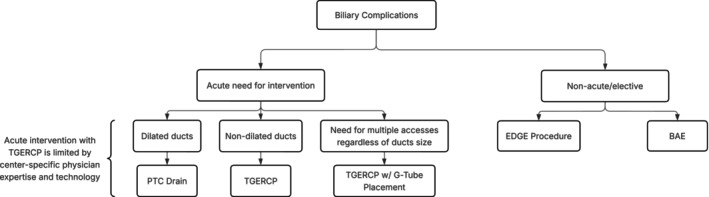

Our single‐center favorable experience with TG‐ERCP is consistent with the current literature around non‐OLTx patients, which notes high success rates of 90%–100% for management of biliary postoperative pathology [ref. 9, ref. 13]. Unfortunately, in the setting of OLTx and RYGB, there is limited literature evaluating biliary interrogation techniques with this method. Given our experience and literature review, we suggest TG‐ERCP is a viable first‐line approach under certain circumstances (Figure 6). TG‐ERCP uses a single port through remnant gastrotomy, which allows for minimal dissection, reducing surgical trauma and avoiding the recently reconstructed portal triad [ref. 18]. It eliminates the higher risk of graft vascular injury by PTC drain placement, particularly in patients with nondilated bile ducts, as well as PTC contraindications of ascites and compromised coagulation [ref. 12, ref. 19]. It overcomes BAE’s lower rate of successful biliary complication management, largely confounded by the challenge of standard cannulation of the intact papilla in RYGB patients [ref. 9, ref. 20]. Further, TG‐ERCP can be performed acutely for potentially life‐threatening biliary complications in the setting of a surgically inaccessible hilum, unlike the two‐staged EDGE procedure that requires approximately 2 weeks of transluminal tract maturation in most instances [ref. 21]. In addition, utilization of the TG‐ERCP placed G‐tube is a solution to future biliary access needs and the requirement for postoperative stent removal. Furthermore, it has the capability to address malnourishment by enteral supplemental nutrition. Finally, TG‐ERCP appears to be a simple procedure in single‐center experiences, after gastric remnant access is established, given the widespread modern adoption of ERCP. In fact, this has the potential to allow for minimization of center‐to‐center variability by lowering both expertise and technological performance thresholds [ref. 10, ref. 13, ref. 18].

TG‐ERCP is not without drawbacks (Table 1). An additional operation is required to facilitate endoscopic access and presents a longer procedure duration. However, this operation can be done laparoscopically or robotically depending on surgeon experience and expertise. In our case, our original goal in returning to the operating room was exploration with possible biliary reconstruction prior to the decision to perform TG‐ERCP. Regardless, we would not recommend prophylactic mobilization of the remnant stomach or G‐tube placement due to the risk of bleeding from the spleen and short gastrics in patients with portal hypertension. Therefore, for patients requiring acute or emergent intervention with either contraindications to PTC drain placement or concurrent need for supplemental enteral nutrition, TG‐ERCP should be first‐line intervention.